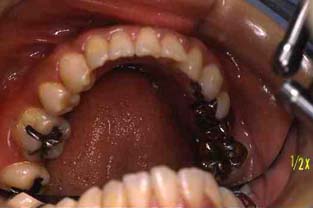

成人その3:八重歯と顎が狭い(唇側低位咬合,歯列狭窄) 22才,女性

矯正後(一年10ヶ月後)

上顎

(ミラー像)